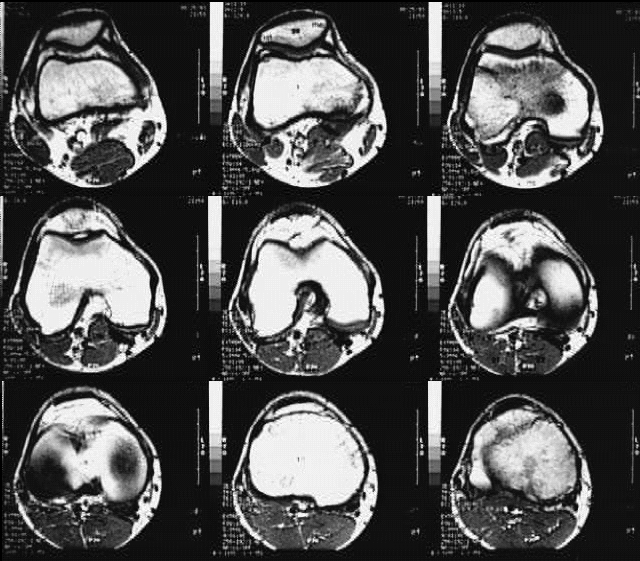

Radiology Images

Lower Limbs: Knee MRI Cross